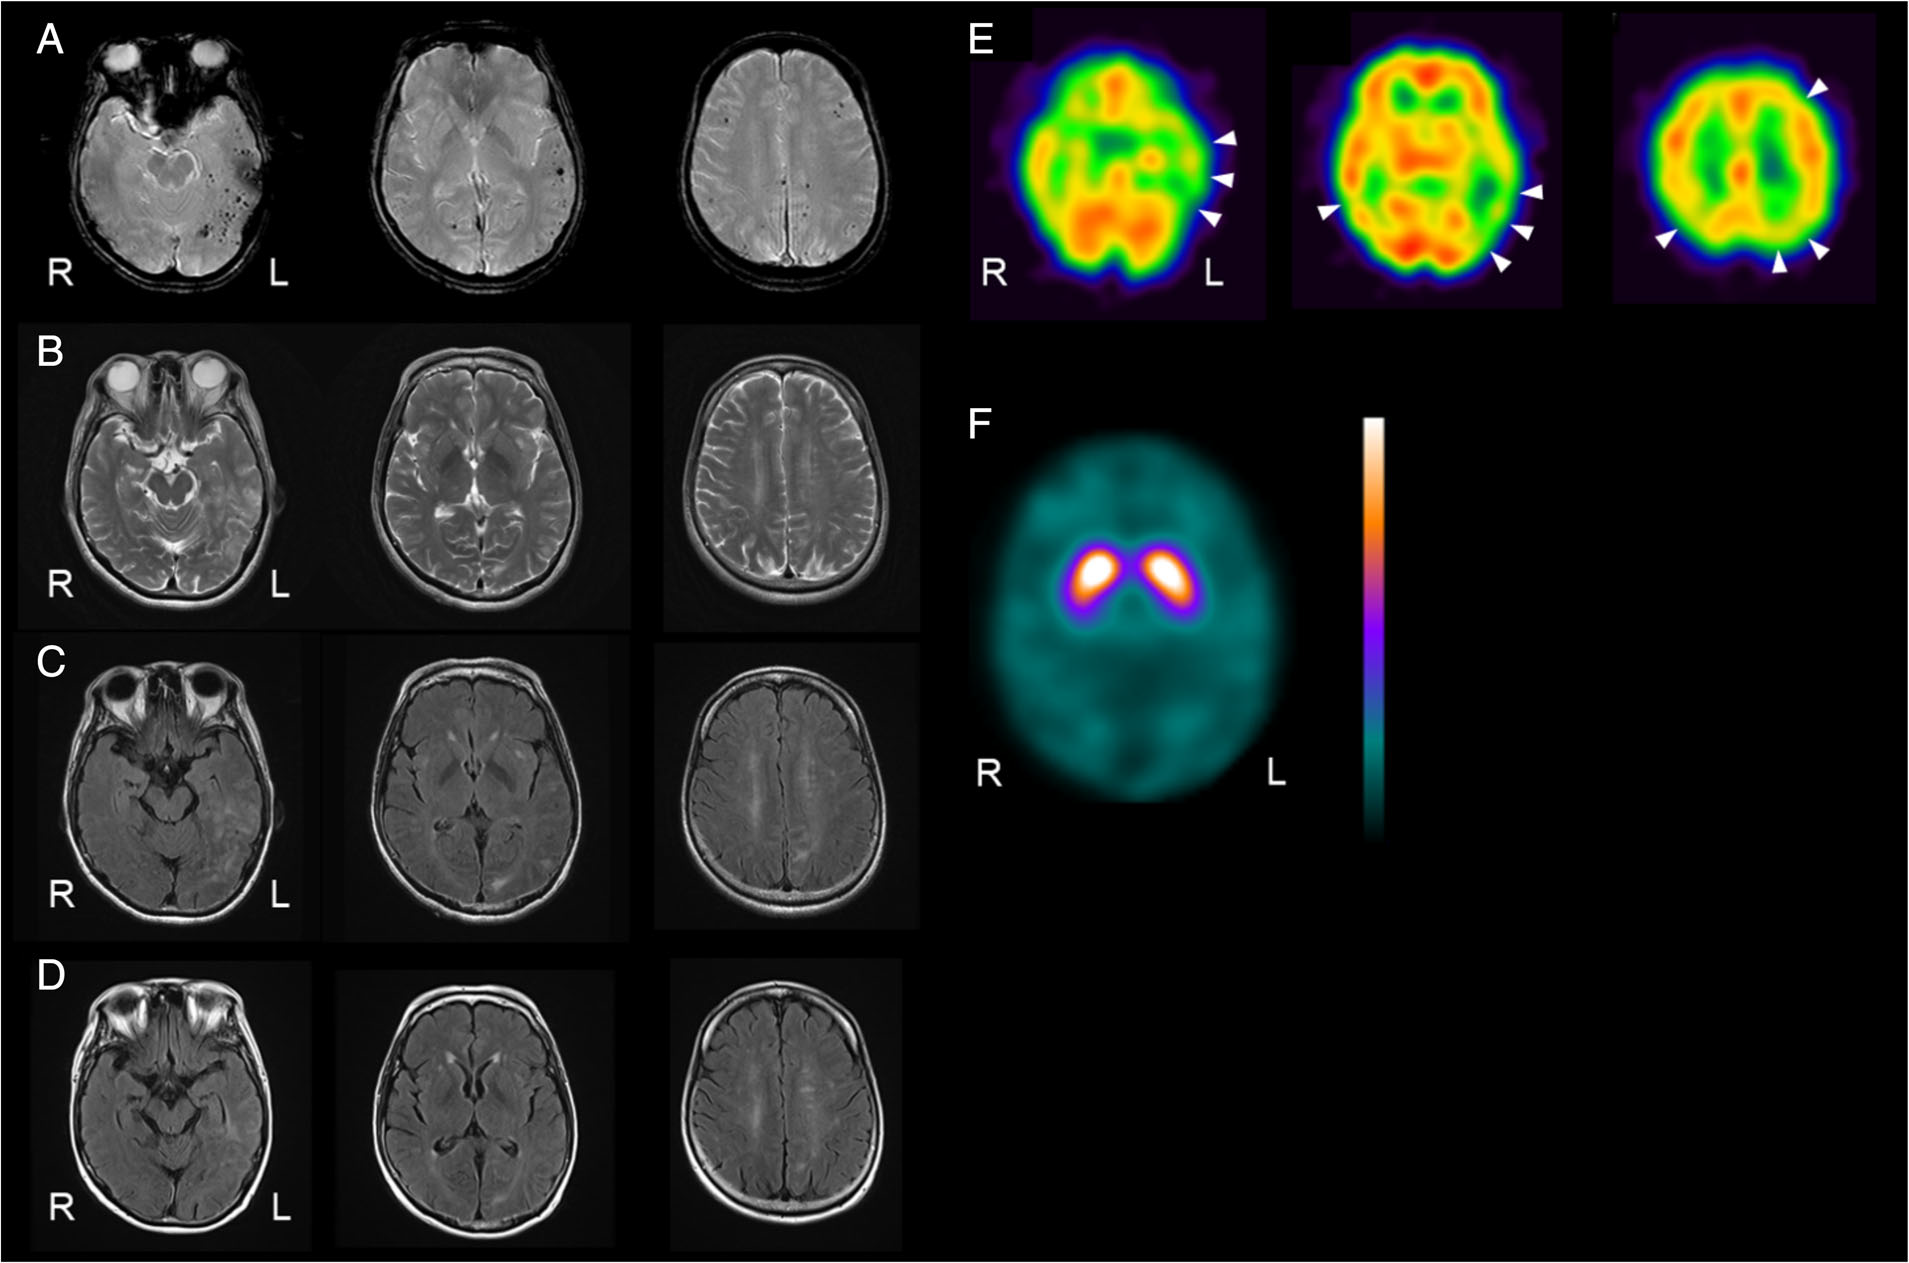

Т1 т2 flair

Т1 т2 flair 116 фотографий